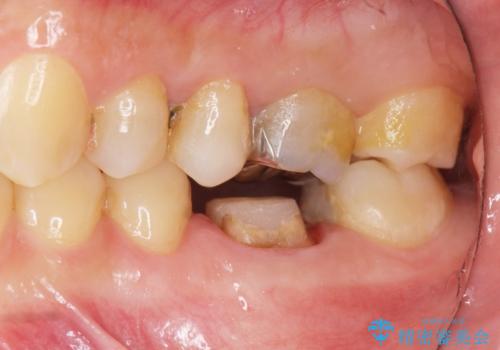

放置してしまった歯 根管治療からの機能回復

- 放置してしまった歯が痛み、いよいよ耐えられなくなり来院されました。

根管治療の途中で放置してしまっていた歯を、最終的に機能回復できるよう治療を行っていきます。

治療途中の歯の放置は、より虫歯を進行させてしまい抜歯に至ってしまうこともあるので注意が必要です。